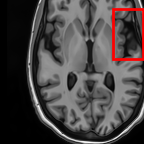

Sparsity Ikzsubscriptsuperscript𝐼𝑧absent𝑘I^{z}_{\downarrow k} LI 2D CNN 3D CNN Ours GT Ikz+1subscriptsuperscript𝐼𝑧1absent𝑘I^{z+1}_{\downarrow k}

4 Refer to caption Refer to caption Refer to caption Refer to caption Refer to caption Refer to caption Refer to caption

Refer to caption Refer to caption (a) 27.37/0.8465 Refer to caption (b) 32.34/0.9441 Refer to caption (c) 32.72/0.9436 Refer to caption (d) 34.11/0.9607 Refer to caption (e) PSNR(dB)/SSIM Refer to caption

Figure 5: Visual comparisons of slice interpolation approaches. For 4x sparsity, the second of three interpolated MR slices is presented. For 8x sparsity, the third of seven interpolated slices is presented.

In Fig. 5, we present the observed slices Ikzsuperscriptsubscript𝐼absent𝑘𝑧I_{\downarrow k}^{z} and Ikz+1superscriptsubscript𝐼absent𝑘𝑧1I_{\downarrow k}^{z+1} along with the interpolated slices produced by different methods. Specifically we demonstrate the second of three interpolated MR slices for 4x sparsity, and the third of seven interpolated slices for 8x sparsity. We highlight the region where the anatomical structures significantly change compared to the observed slices Ikzsubscriptsuperscript𝐼𝑧absent𝑘I^{z}_{\downarrow k} and Ikz+1subscriptsuperscript𝐼𝑧1absent𝑘I^{z+1}_{\downarrow k}. We observe that although 2D CNN has comparable performance in terms of PSNR and SSIM, it tends to produce false anatomical structures in the zoomed regions. 3D CNN is able to resolve more accurate details. However, the improvement is quite limited, which we attribute to the fact that 3D CNN requires more training MR volumes in order to generalize and has smaller receptive field due to patch-based training. Our method benefits from the large receptive field of 2D CNN and two-view fusion, which not only produces sharper images, but also correctly estimates brain anatomy. The sharp and accurate estimation is crucial in clinical applications such as diagnosing Alzheimer’s Disease by brain volume estimation.